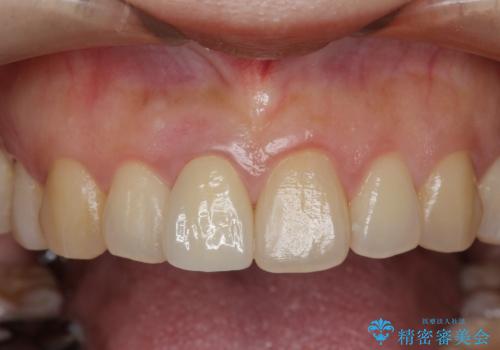

- 幼少期に前歯をぶつけて歯が折れ、神経の治療・クラウン治療を行った。グラつきと見た目の改善を希望して来院されました。

精密な仮歯をいれ、歯周組織を整えるとともにファイバーコア築盛、シェードテイキングを行い見た目に自然なジルコニアクラウンを製作していきます。

ジルコニアクラウンの中でも当法人のグレードの高い、スペシャル・エクセレントプランはオーダーメイドで色調を合わせることで周囲の歯に馴染んだ自然な歯を製作することのできるプランです。